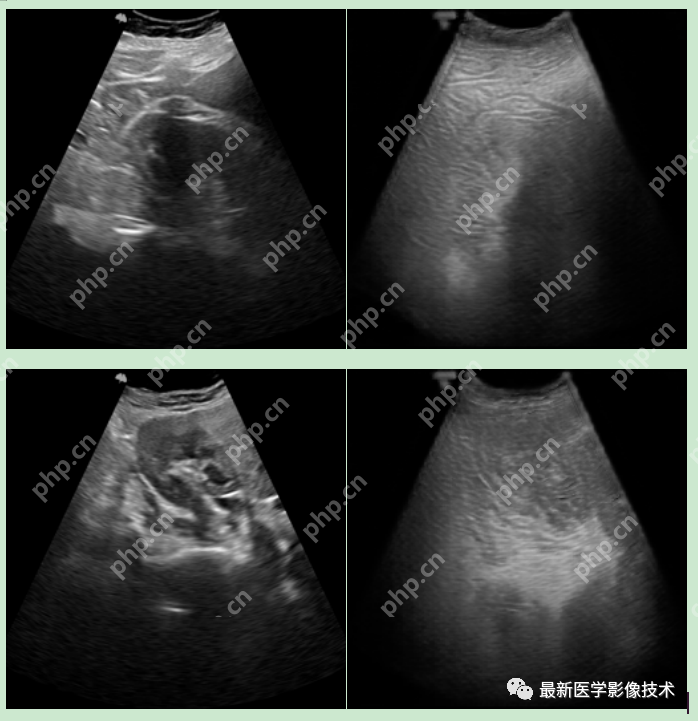

6、测试集部分生成结果

左图为低质量图像,右图为生成的高质量图像。